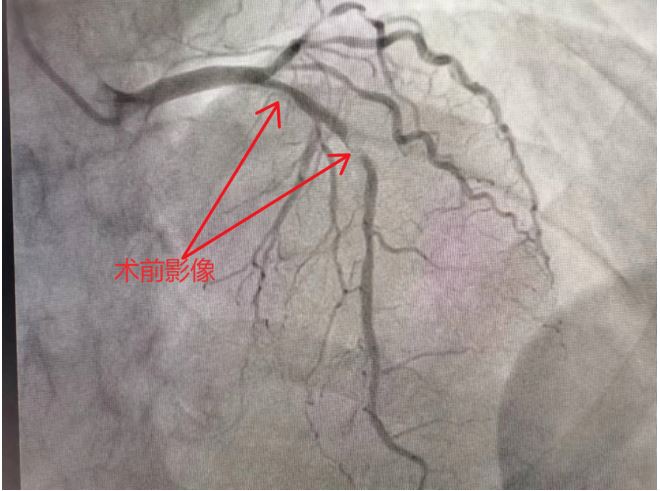

患者,胡某,男,66岁,以活动后胸闷伴颈部紧缩感20余天于2024.01.25入院,既往有糖尿病史4年余,高甘油三酯血症10余年,完善检查后于2024.01.26行冠脉造影示:冠心病,三支病变,均伴严重钙化,其中前降支近中段全部钙化,狭窄最重95%。面对这种病变,我们该怎么办呢?

针对该患者,我们选择处理前降支病变,依据冠脉造影结果提示冠脉钙化极有可能为环形钙化,因此我们应对其进行血管内超声评估。因冠脉狭窄极重,超声导管无法通过狭窄病变,我们用普通球囊对钙化病变进行预扩张,之后行超声检查示:前降支中段、近段至左主干末段可见连续性粥样硬化伴钙化,且大部分为环形钙化,且部分钙化管腔直径偏大,常规旋磨头无法有效旋磨。此时,针对钙化病变另一介入设备便闪亮登场了,那便是我们的冲击波球囊,别看它小,它专碎石头,秉性欺硬不伤软。

充分与患者家属沟通并取得患者家属同意后,济源二院薛瑞璐主任介入团队便开始了冠脉内冲击波诊治。将3.5*12mm冲击波球囊送至前降支中段,定位后释放脉冲(工作压力4atm、扩张压力6atm),由中段逐渐移行到LAD开口,共8个周期,其中对中段严重钙化病变处重点处理,术后即可便呈现满意的管腔,复查血管内超声发现:环形钙化处均出现了裂隙。后经高压扩张,最后在前降支植入2枚支架,超声提示:支架贴壁良好,膨胀满意,术中患者无特殊不适。